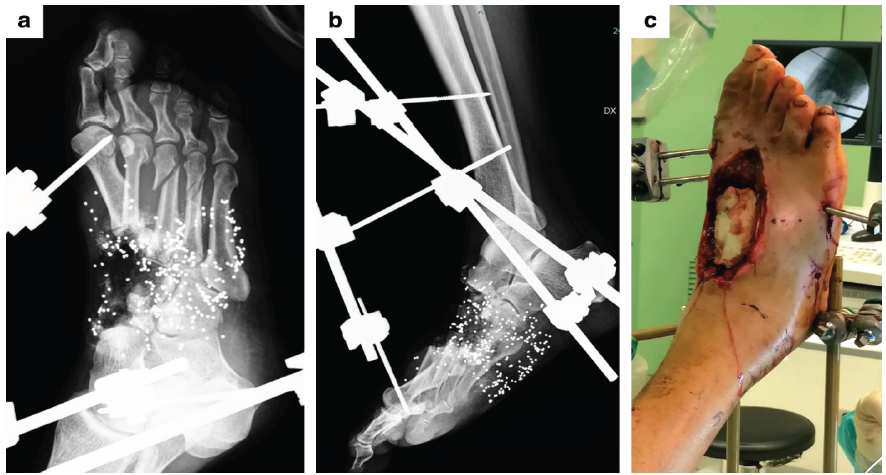

Figure 1: Case 1. (a and b) Radiographic images after the first surgical procedure of debridement and stabilization with an external fixator. (c) Clinical photograph showing the dorsal soft-tissue defect after placement of antibiotic-loaded cement.

A 61-year-old male hunter was transferred to Sant’Anna Hospital in Como (Italy) from an orthopedic center in Croatia, where he had been treated 1 week earlier with local debridement and provisional external fixation following a short-distance (50 cm) smoothbore shotgun injury to the right foot during a hunting accident. On admission, the patient presented with a dorsal soft-tissue defect measuring 35 cm2 and a plantar defect of 18 cm2. X-rays revealed extensive bone loss, including the first, second, and third cuneiforms, the navicular bone, and the bases of the first and second metatarsals. Fractures of the third and fourth metatarsals and the proximal phalanx of the great toe were also observed, along with retention of multiple lead pellets. Computed tomography (CT) angiography showed no significant vascular damage, with patency of the anterior tibial, posterior tibial, interosseous, and dorsalis pedis arteries. Immediate local debridement and removal of visible lead pellets were performed, followed 2 days later by a second-look procedure. This included removal of devitalized bone fragments from the navicular, metatarsals, and cuneiform bones, removal of the previously applied external fixator, and stabilization with a Hoffmann 3 (Stryker) external fixator spanning from the distal tibia to the rearfoot (calcaneal tuberosity) and forefoot (first and fifth metatarsals). Gentamicin-loaded bone cement (Refobacin Bone Cement R, Zimmer Biomet) was interposed into the bone defects, covered with a reverse sural artery pedicle flap (Fig. 1). Vacuum-assisted closure (VAC) therapy was also applied.